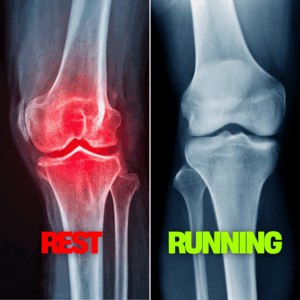

[Read more...] about Rest Didn’t Fix Tim’s Knee Pain (Running Did)

In this episode, Matthew Boyd discusses the relationship between running and knee arthritis, debunking the myth that running exacerbates arthritis. He …

[Read more...] about Rest from Running Makes Knee Arthritis Worse